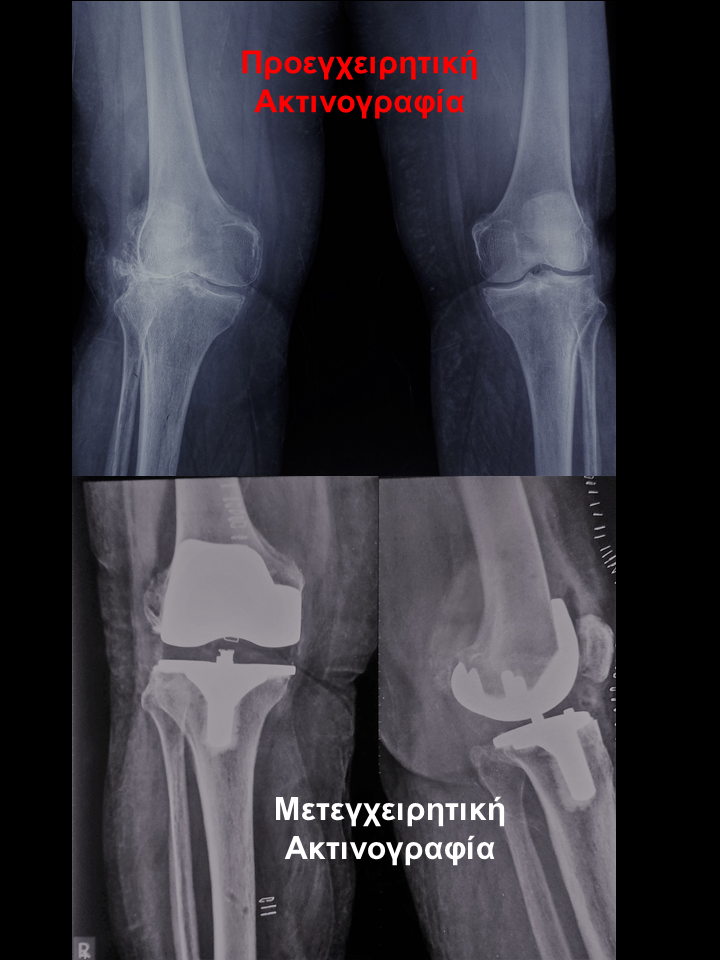

Ρομποτική αρθροπλαστική και στα 2 γόνατα στο ίδιο χειρουργείο

Ασθενής 75 χρονών με οστεοαρθρίτιδα και στα 2 γόνατα. Είχε επιδεινούμενο άλγος τα τελευταία 2 χρόνια που την δυσκόλευε στη βάδιση και την αφυπνούσε το βράδυ. Υπεβλήθη σε ρομποτική αρθροπλαστική και στα 2 γόνατα την ίδια ημέρα. Χρησιμοποιήθηκε η τεχνική διατήρησης οστού όπου αφαιρέθηκαν λιγότερα χιλιοστά οστού. Ο άξονας στο αριστερό γόνατο από 100 αποκαταστάθηκε στις 00 και ομοίως στο δεξί. Η κάμψη στο αριστερό αποκαταστάθηκε στις 1160 . Η ασθενής βαδίζει πλέον χωρίς καμία ενόχληση.